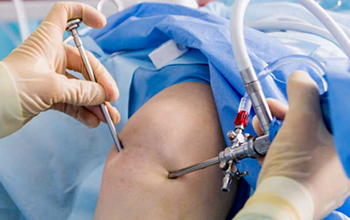

Our Orthopedics Department provides comprehensive care for disorders and injuries affecting the bones, joints, muscles, ligaments, and spine. With experienced orthopedic Read More